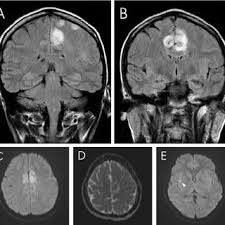

Two subtypes are recognised which differ in demographics, virus, and pattern of involvement. Mri demonstrates extensive edema in the right temporal lobe with areas of intrinsic high t1 signal, in keeping with hemorrhage. Terminology the entity or closely related variants have also been. Coccidioidal meningitis refers to central nervous system involvement of the dimorphic fungus coccidioides spp, mainly coccidioides immitis and coccidioides posadasi. Note the high signal in the caudate heads and putamen on flair.

Pcr was repeated on the biopsy specimen and was positive for hsv. Limbic encephalitis, mca ischaemia, tumours, effects of seizures) hyperintense t2 signal in the medial temporal lobes, inferior frontal lobes and insula basal ganglia are usually spared Axial t2 prominent swelling, increase t2 signal involving the left temporal lobe and insular cortex. Multilocularis, and describes a spectrum of disease involving the spinal cord, the spine, or both. Mri is the diagnostic modality of choice abnormal in 90%; A brain biopsy was performed and the histology was consistent with encephalitis. Mri demonstrates extensive edema in the right temporal lobe with areas of intrinsic high t1 signal, in keeping with hemorrhage. For a general discussion, and for links to other system specific manifestations, please refer to the article on hydatid disease.

The basal ganglia are usually spared. Mri is the diagnostic modality of choice abnormal in 90%; Hsv encephalitis | radiology case | radiopaedia.org. Axial t2 prominent swelling, increase t2 signal involving the left temporal lobe and insular cortex. For a general discussion, and for links to other system specific manifestations, please refer to the article on hydatid disease. Herpes simplex (hsv) encephalitis is the most common cause of fatal sporadic fulminant necrotizing viral encephalitis and has characteristic imaging findings. Herpes simplex virus (hsv) is a human herpesvirus that causes hsv encephalitis (hse), which is the commonest fatal sporadic encephalitis in humans. Hse may result from primary infection or reactivation from latency, and it frequently involves frontal or temporal lobes, as well as the brain stem. The differential diagnoses include limbic encephalitis (paraneoplastic), gliomatosis cerebri, and status epilepticus. A brain biopsy was performed and the histology was consistent with encephalitis. For a general discussion, and for links to other system specific manifestations, please refer to the article on hydatid disease. Cerebral malaria is a rare intracranial complication of a malarial infection. Bilateral temporal lobe t2 hyperintensity refers to hyperintense signal involving the temporal lobes on t2 weighted and flair imaging.

Two subtypes are recognised which differ in demographics, virus, and pattern of involvement. Terminology cerebritis is essentially the same as encephalitis except that it is used to denote brain par. There is also some cortical ribboning seen on dwi. Hsv encephalitis | radiology case | radiopaedia.org. Herpes simplex encephalitis (hse) is the most common form of viral sporadic encephalitis and, when left untreated, has a mortality rate of 70% (3, 22).